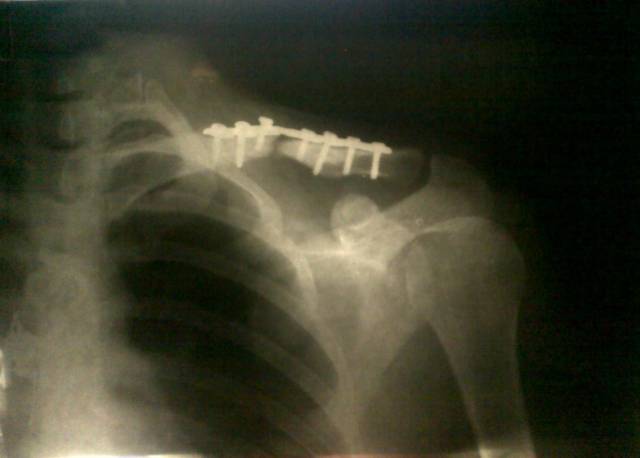

Как бы ложный сустав не образовался, очень уж явное расстояние между краями.

Оскольчатый?

оскольчатый, все поотрывалось, стягивали как могли. Пока катают на руле)) номер один - УЧИТЕСЬ ПАДАТЬ!!!

На фото жесть какая то, репозиция кривая, осколки в километре друг от друга... А пластины разные бывают, есть хорошие, приличные нагрузки держат, а есть "пластилин", трещат пополам от того, что ведро с водой в руке с пластиной пронес...

тебе пластину чё, с бодуна ставили? Отломки как то криво соединили...